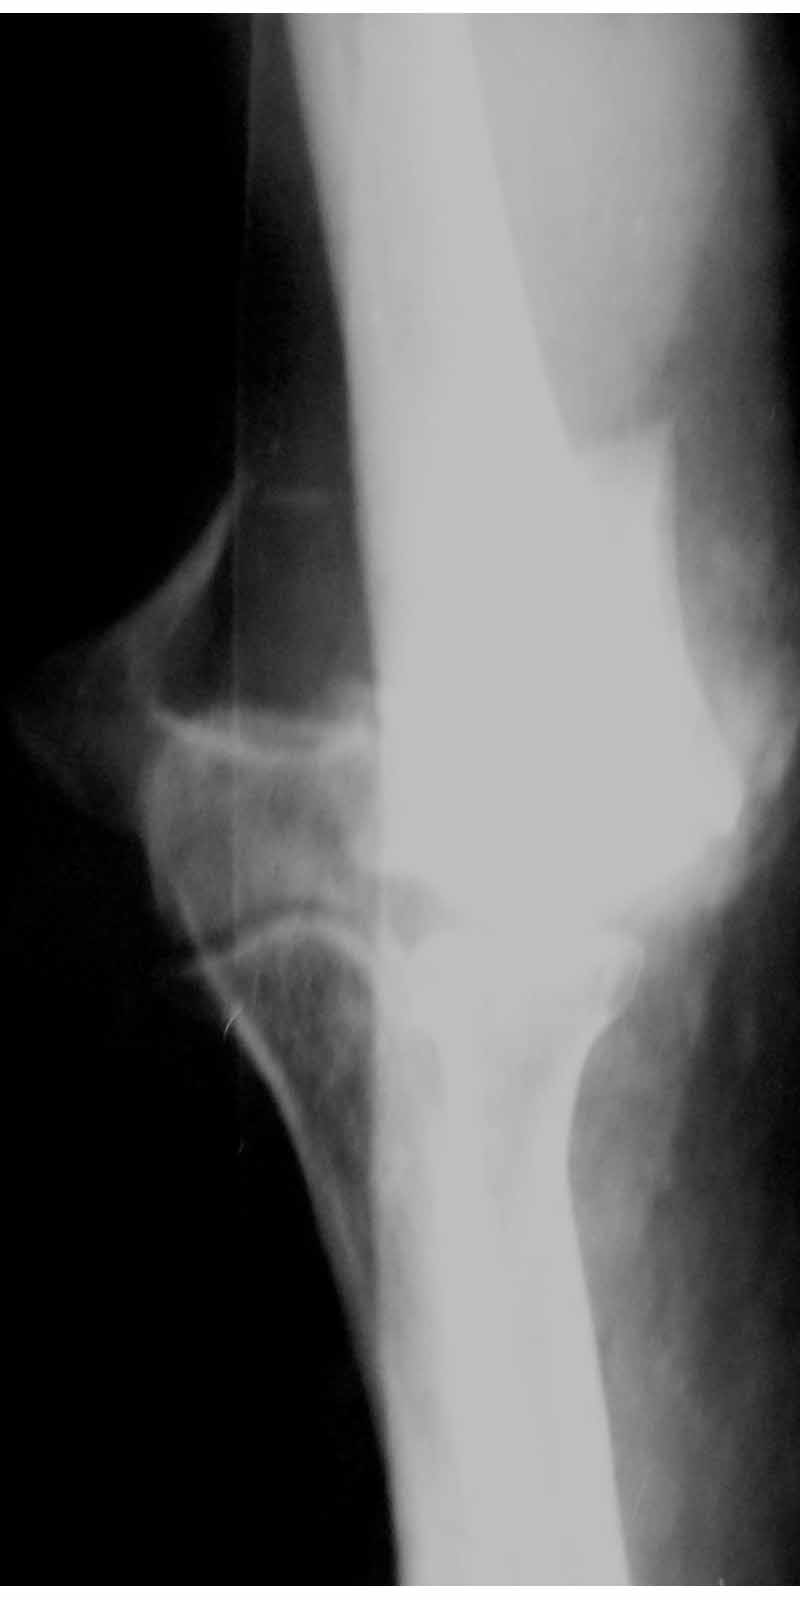

Alexander Artemiev 14 Сентябрь 2005, 16:19

Женщина 42 лет, операция через неделю после перелома.

Д-з - открытый перелом мыщелков со смещзением и локтевой кости

без смещения - падение с лошади.

До операции снимки не очень, тем более в гипсе.

Остеосинтез закрытый (если так можно выразиться), т.е. без

разрезов. Длительность операции - около 1,5 часа со студентом.

6 щелчков ЭОПом.